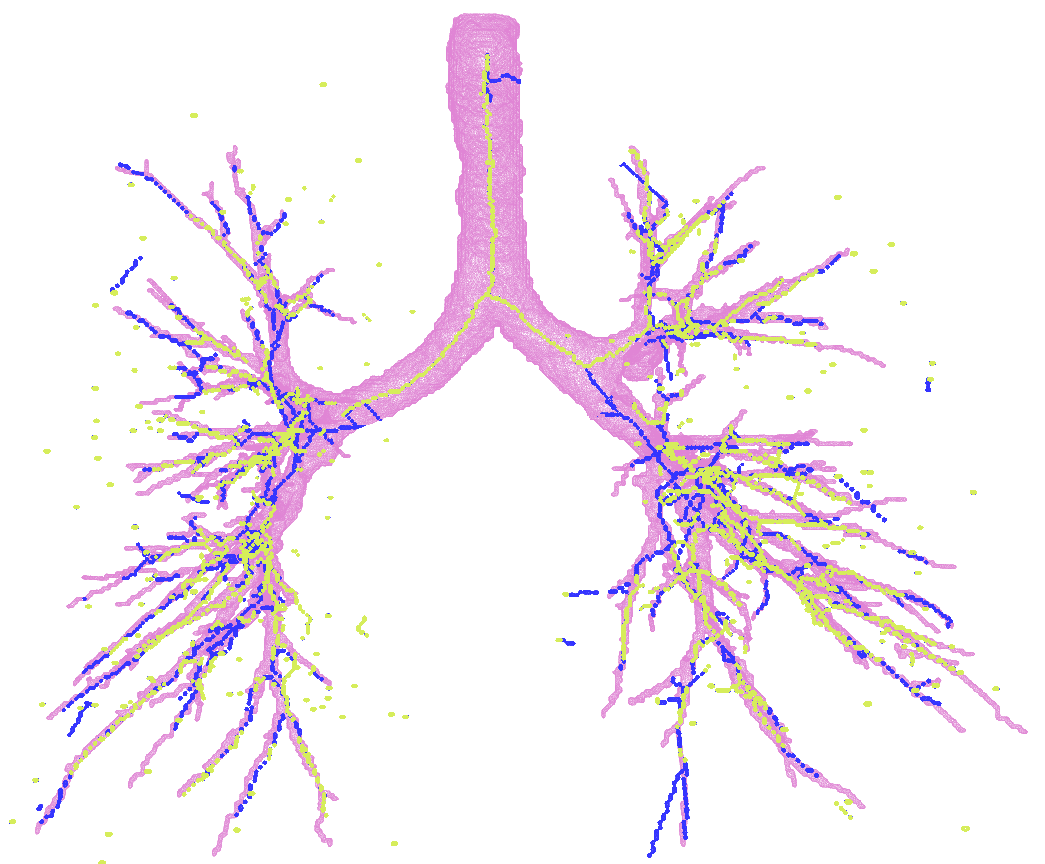

Results Experiments comparing GNN and MFN models were conducted on the reference scans split into for training and for test purposes. Table 1 summarises centerline distance error, , on the test set. We show two versions of the GNN model: a stand-alone model (GNN) and with merged predictions from MFN (GNN+MFN), obtained from union of the predictions from both methods. Visualisation of MFN and GNN predictions on one test set image along with the reference segmentations is shown in Figure 1(b).